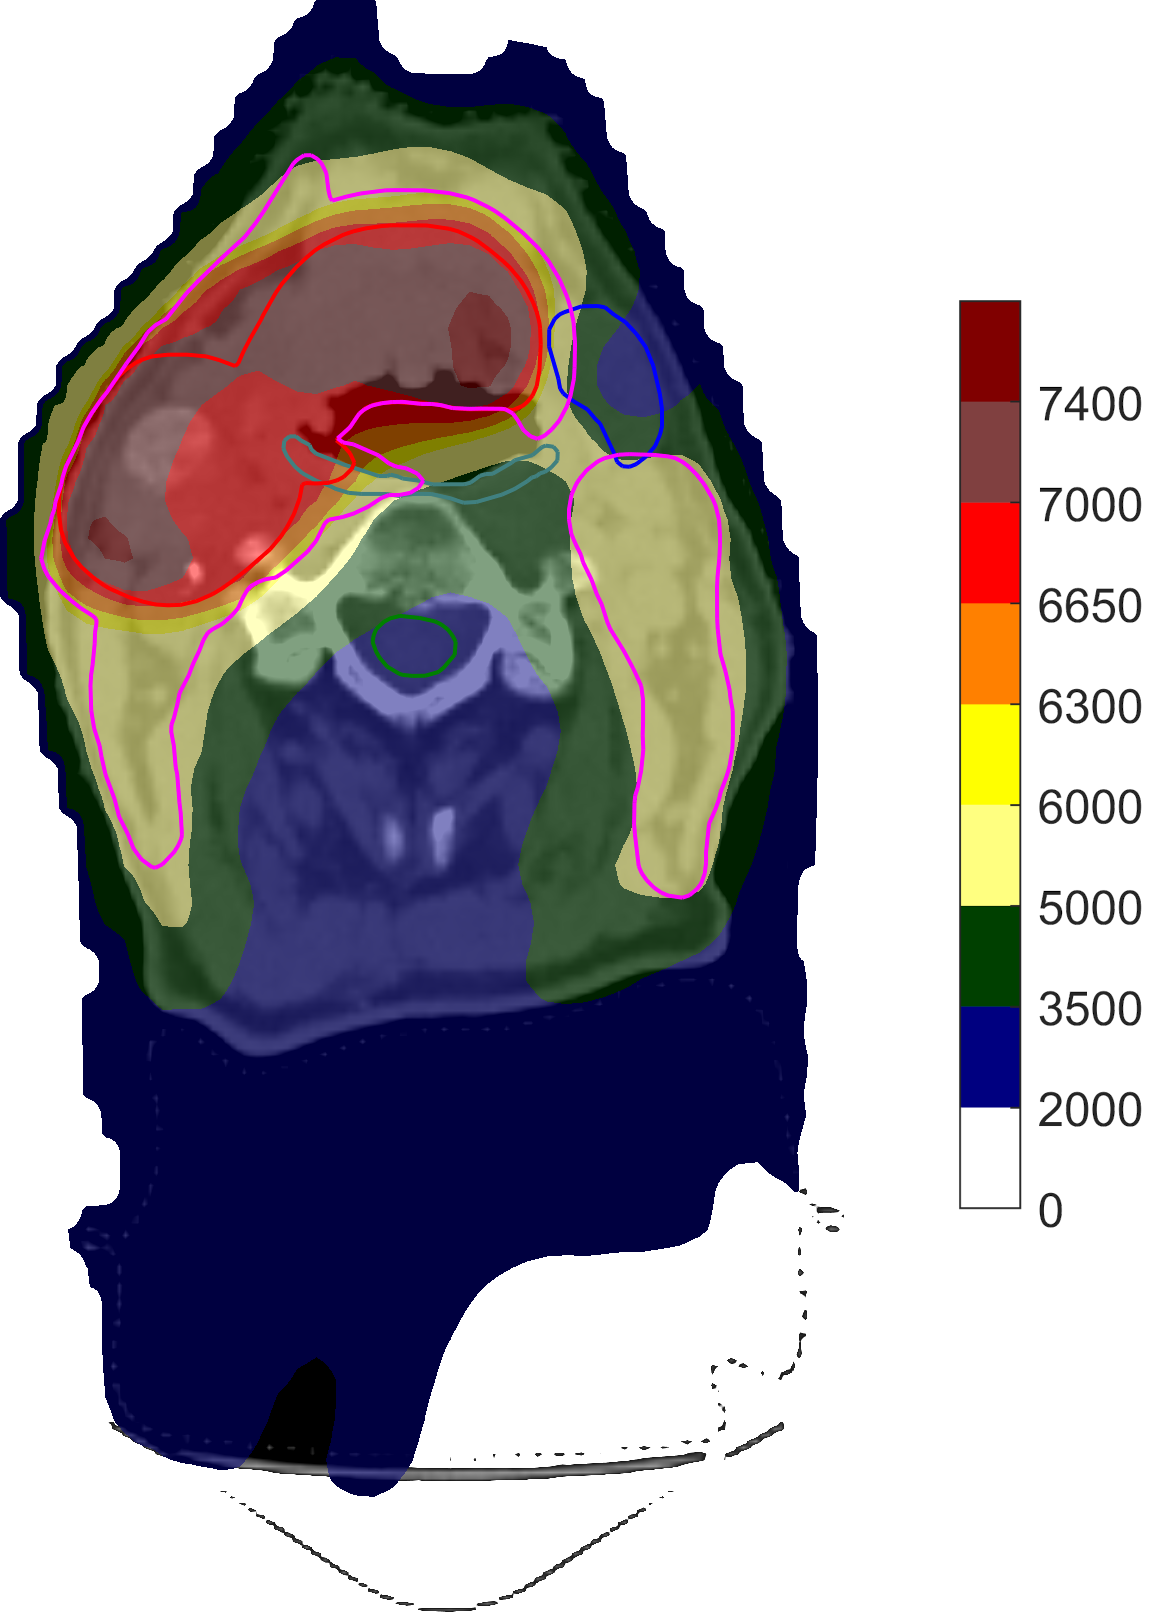

For the mostly constrained formulation, all optimizations started in the solution to the unconstrained formulation obtained from the direct optimization of clinical goals with mean-tail-dose, which was feasible with respect to all constraints. We chose the run using w~C2=105superscriptsubscript~𝑤𝐶2superscript105\widetilde{w}_{C}^{2}=10^{5}, which achieved the best overall plan quality of all values tried, to compare to the direct optimization—Table 7 shows the respective clinical goal levels after optimization and Figure 6 shows the corresponding DVHs and spatial dose distributions. While the degrees of constraint infeasibility were similar, the direct optimization was able to lower the mean dose to the middle and superior PCMs significantly better than using the conventional functions. In particular, it was observed that the optimization using the conventional formulation quickly converged while that using the direct formulation was able to steadily push the mean doses down, again showcasing the problems with vanishing gradients associated with the conventional penalty functions.

Refer to caption

(a)

(b)

(c)

Figure 6: Transversal cuts of the spatial dose distributions of the optimized plans obtained for the constrained head-and-neck test using the conventional formulation (a) and using the direct optimization of clinical goals (b). A DVH comparison between the former (dashed) and the latter (solid) is shown in (c).